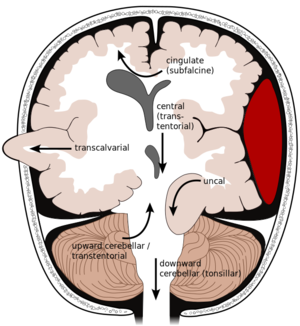

2ـ النزيف تحت العنكبوتية subarachnoid hemorrhage: يقدر بنحو 5% من الأمراض الوعائية الدماغية. وفيه يحدث نزيف حول التلافيف الدماغية (وخاصة تحت الطبقة السحائية المغطية لسطح الدماغ المعروفة باسم العنكبوتية).

ـ عوامل الخطورة والأسباب: من أهم الأسباب المؤدية لهذا النوع من النزيف رضوض الدماغ والتشوهات الوعائية الدماغية (ولاسيما أمهات الدم والتشوهات الشريانية الوريدية) ومن عوامل الخطورة أيضاً فرط الضغط الشرياني والتدخين.

ـ الأعراض والتشخيص: تتمثل الأعراض التقليدية للنزف تحت العنكبوتية بحدوث صداع مفاجئ شديد كثيراً ما يصفه المريض بأنه «أسوأ صداع خبره على الإطلاق»، وكثيراً ما يترافق الصداع مع غثيان وإقياء ويتبعه حدوث صلابة في النقرة مع اختلاجات وسبات أحياناً.

وقد يسبق حدوث النزف ما يدعى بالعلامات التحذيرية warning signs كالرؤية المزدوجة والصداع الخفيف نسبياً، وتنتج هذه الأعراض عن الضغط الذي تسببه أم الدم (مثلاً) على أحد أعصاب العين أو حدوث نزيف خفيف منها قبل تمزقها الذي قد يؤدي إلى نزيف شديد قاتل.

أما التشخيص فقد يعتمد على عدة إجراءات منها تصوير الدماغ (الطبقي المحوري وأحياناً المرنان المغنطيسي) أو إجراء بزل قطني لتحري وجود الدم في السائل الدماغي الشوكي. ومن الإجراءات المهمة تصوير الشرايين الدماغية (بوساطة القثطرة) للتحري عن وجود تشوهات وعائية.